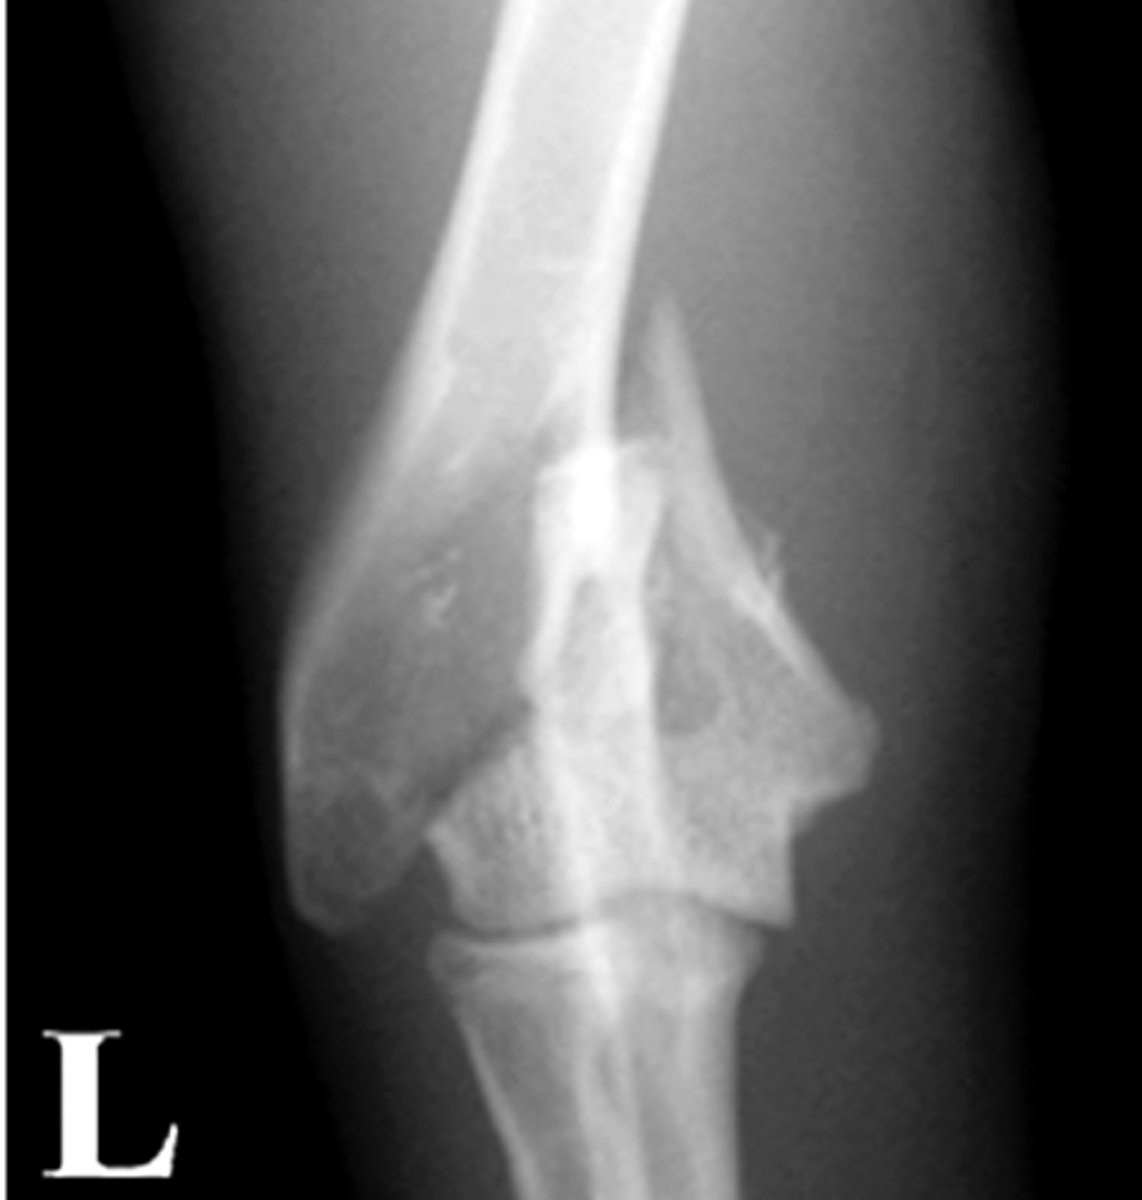

Grade the Salter-Harris fracture?

Grade 2 - fracture through the physis

Above the physis

Grade 3 - fracture through the physis and epiphysis

beLow the physis